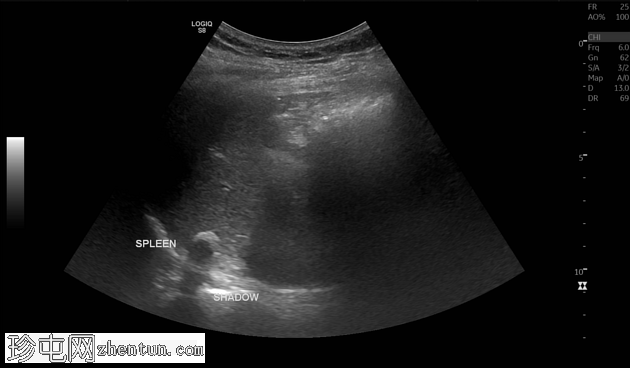

超声

纵切面

脾脏大小正常,纵轴约8.15厘米。脾实质内可见一孤立、边界清晰的高回声灶,符合钙化表现。该钙化灶后方可见声影,未见相关肿块、囊肿或血管异常。无脾周积液或脾肿大。

其余上腹部结构未见异常。